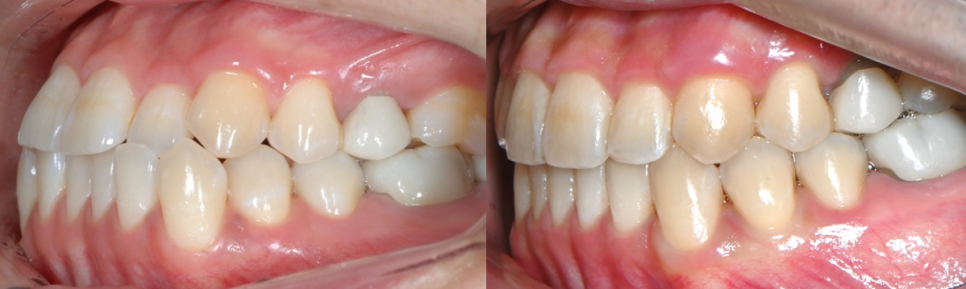

악궁이 점점 확장되면서 삐뚤빼뚤했던 치열들이 가지런하게 배열되고,

윗니 아랫니 사이의 공간이 점점 닫히며,

반대교합이 개선되면서 정상적인 교합으로

변하고 있는 모습을 확인해 보실 수 있습니다 ^^

윗니와 아랫니 사이의 틈이 사라지고,

윗니를 덮고 있던 아랫니들이 제 위치를 찾으며 부정교합이 개선되었을 뿐만 아니라

정중앙선이 일치하도록 마무리 해드렸습니다 :)

인비절라인으로 교정 후

위, 아랫니 사이에 틈이 줄어들면서 발음이 개선되고

구강 내 각자의 역할을 조화롭게 도와주어

기능적인 부분을 회복 하실 수 있었어요 :)